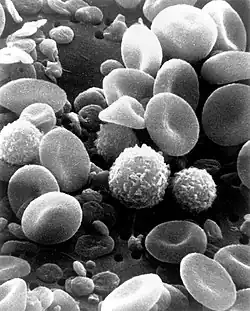

| 9×10−18 | Average volume of a platelet |

| 9×10−17 | Normal volume of a human red blood cell |

| 2×10−16 | Average volume of a lymphocyte |

| 3.3×10−16 | Mean volume of a neutrophil granulocyte |

| 4.2×10−16 | Volume of an average monocyte |